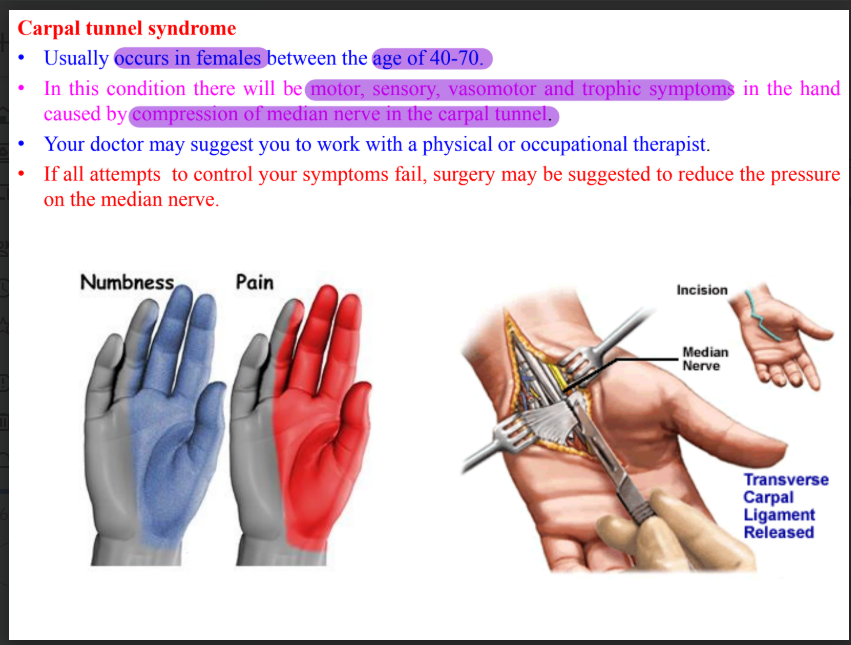

Flexor retinaculum

Fibrous band which bridges anterior concavity of carpals and creates a tunnel

Attachment

Medially- pisiform bone and hook of hamate

Laterally- tubercle of scaphoid and crest of trapezium

Structures deep

Median nerve

Ulnar bursa

Tendons of FDS, FPL, FDP

Carpal tunnel syndrome